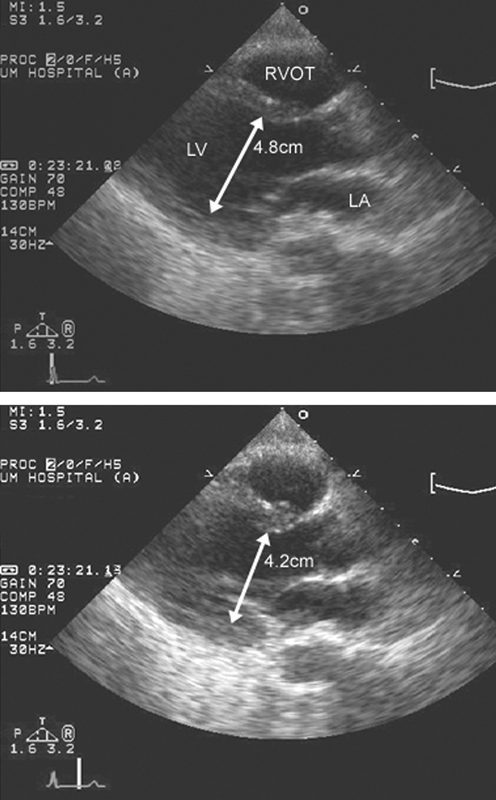

فحوصات تشخيصية لبعض امراض القلب والشرايين التاجية